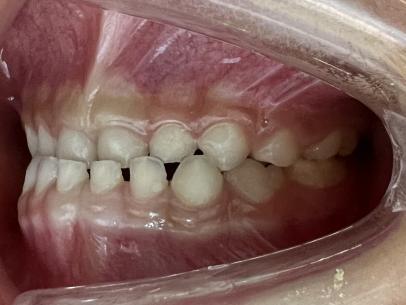

治疗前

治疗后

案例二: